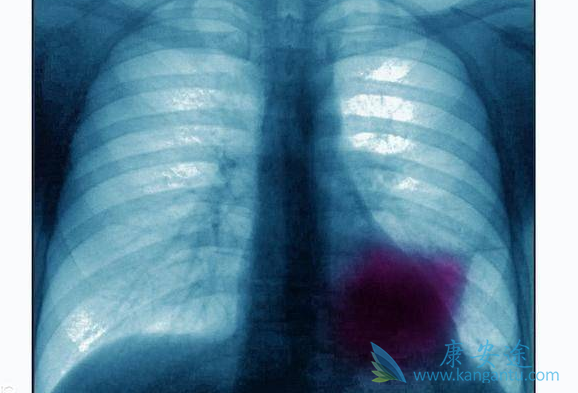

肺癌生物治疗可大大降低晚期肺癌患者的痛苦

晚期肺癌

当人体的免疫系统出现问题,无法彻底清除癌细胞时,肿瘤就会产生。其次,肺部作为人体五脏之华表,一旦发生癌变则会影响整个人体的新陈代谢,而且肺癌极其容易发生转移。肺癌晚期患者手术的风险极高,而且复发的可能性也极大。所以现在医学界普遍对肺癌进行保守治疗,对肿瘤进行控制,防止其转移扩张。只要肿瘤的活性能够被压制,可以保持相对静止状态,并且能够通过药物减少患者的生理痛苦,即使肿瘤无法清除,也不会危及患者生命,这就是医学界提倡的“带瘤生存”。